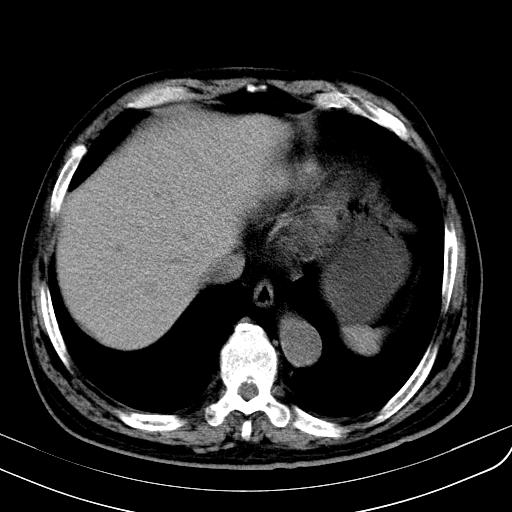

胃底靠近胃大弯处可见一圆形软组织影,直径为3.45cm,ct值约为30.1hu

边缘光滑,密度均匀,良性占位,首先考虑平滑肌瘤。

边缘光滑,密度均匀,良性占位,首先考虑平滑肌瘤。其实平滑肌瘤也是间质瘤的一种